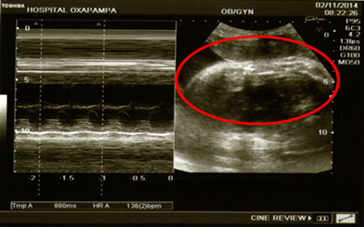

En la hospitalización, luego de aproximadamente 12 horas, se nota quejumbrosa y refiere dolor en flanco derecho, por lo que se decide tomar una ecografía abdominal y transvaginal (Figuras 1 y 2). Donde se llegó a evidenciar: aumento del diámetro apendicular, líquido libre periapendicular e inmovilidad del apéndice.

Según los resultados se presentó: útero grávido, altura uterina 32 cm., situación longitudinal, posición dorso derecho, presentación cefálica. Punto doloroso de Mc Burney (+), Blumberg (+) con el cual se diagnostica abdomen agudo quirúrgico y posible apendicitis aguda complicada, el cual se relaciona estrechamente con sus exámenes de laboratorio.